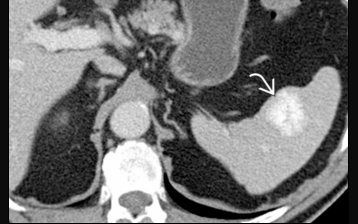

Hemangiome

Le plus fréquent

Généralement < 2cm

CT: Homogene kystique ou solide

Réaussements, Calcifications, Portions kystiques (30%)

IRM: Comme dans le foie (hyperT2, remplissage arteriel puis veineux), mais on voit rarement le remplissage en motte periphérique)

Angiomatose générale = Syndrome de Klippel-Trenaunay-Weber